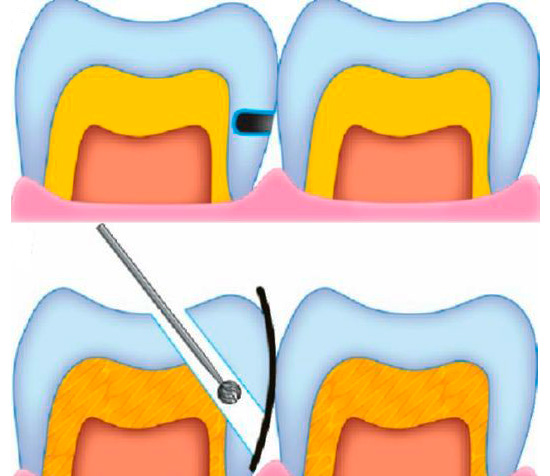

Le immagini seguenti mostrano esempi di preparazione di cavità: